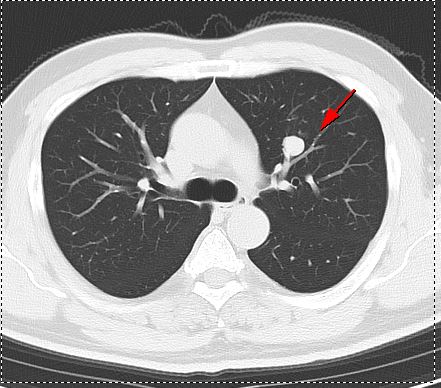

▲早期右乳癌